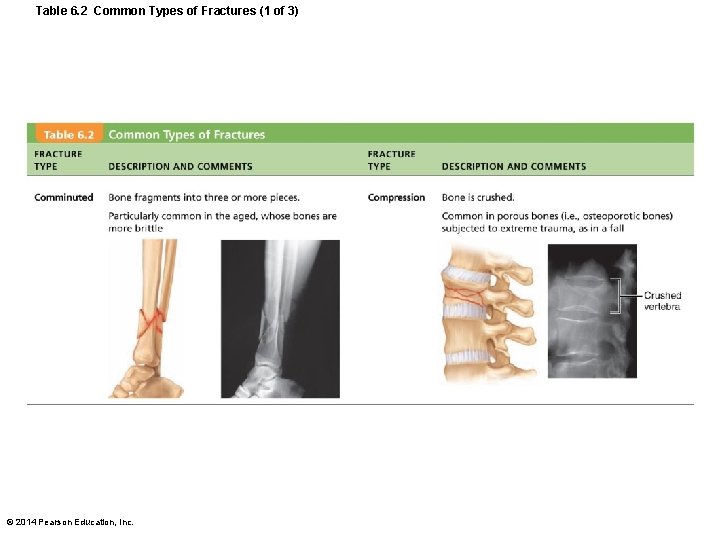

Table 6. 2 Common Types of Fractures (1 of 3) © 2014 Pearson Education, Inc.